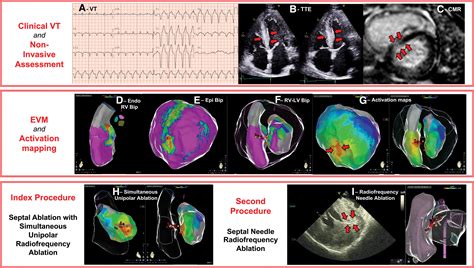

3. Mapping the Heart: The catheter is used to map the electrical activity of the heart. This helps the cardiologist identify the specific areas causing the abnormal heart rhythm.

4. Ablation: Once the problematic areas are identified, the catheter delivers radiofrequency energy or cryoenergy to destroy the abnormal tissue. This process is carefully monitored to ensure the correct areas are targeted.

SVT Tachycardia Ablation is a procedure designed to correct the abnormal electrical pathways in the heart that cause SVT. During the procedure, a catheter is inserted into a blood vessel, typically in the groin, and guided to the heart. The catheter delivers radiofrequency energy or cryoenergy to the specific areas of the heart tissue that are causing the abnormal heart rhythm. This energy destroys the problematic tissue, effectively eliminating the source of the SVT.